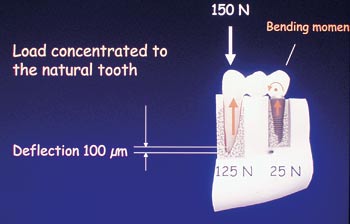

Bakgrunden till problemställningen är, att den naturliga tanden har en avsevärt större rörlighet i benet jämfört med implantatet. Vid belastning av den tandburna brodelen överföres därför en stor del av spänningen till implantatet (Fig. 1). Senare tids kliniska studier har dock visat, att vid korrekt problemhantering kan dessa risker minimeras.

Fig. 1. Belastning på tand och implantat.